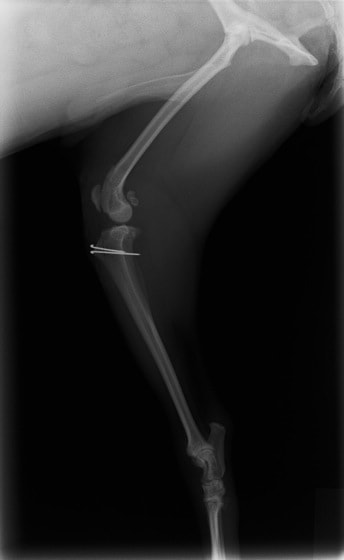

■ 症例22 ポメラニアン 1歳5か月 去勢雄

左後肢の挙上を主訴に来院した。整形学的検査、レントゲン検査より左右の膝蓋骨脱臼(左GradeⅡ〜Ⅲ、右Grade Ⅱ)を認めた。また、脛骨の前方引き出し試験の際に、引き出し兆候は認められないものの、疼痛が認められたため、前十字靭帯の損傷が疑われた。術中における、目視および関節内の操作によって、前十字靭帯の損傷や過伸展といった異常が認められなかったため、膝蓋骨脱臼の整復のみ実施した。手術手技は縫工筋及び内側広筋の解放、脛骨粗面の外側転位、滑車ブロック形造溝術、内外側関節包の縫縮を実施した。本症例は跛行もなく経過良好である。しかし、頸骨高平部の角度(TPA)が 右26.2°、左24.9°であり、解剖学的に前十字靭帯損傷のリスクが高いことから今後の経過に注意が必要である。